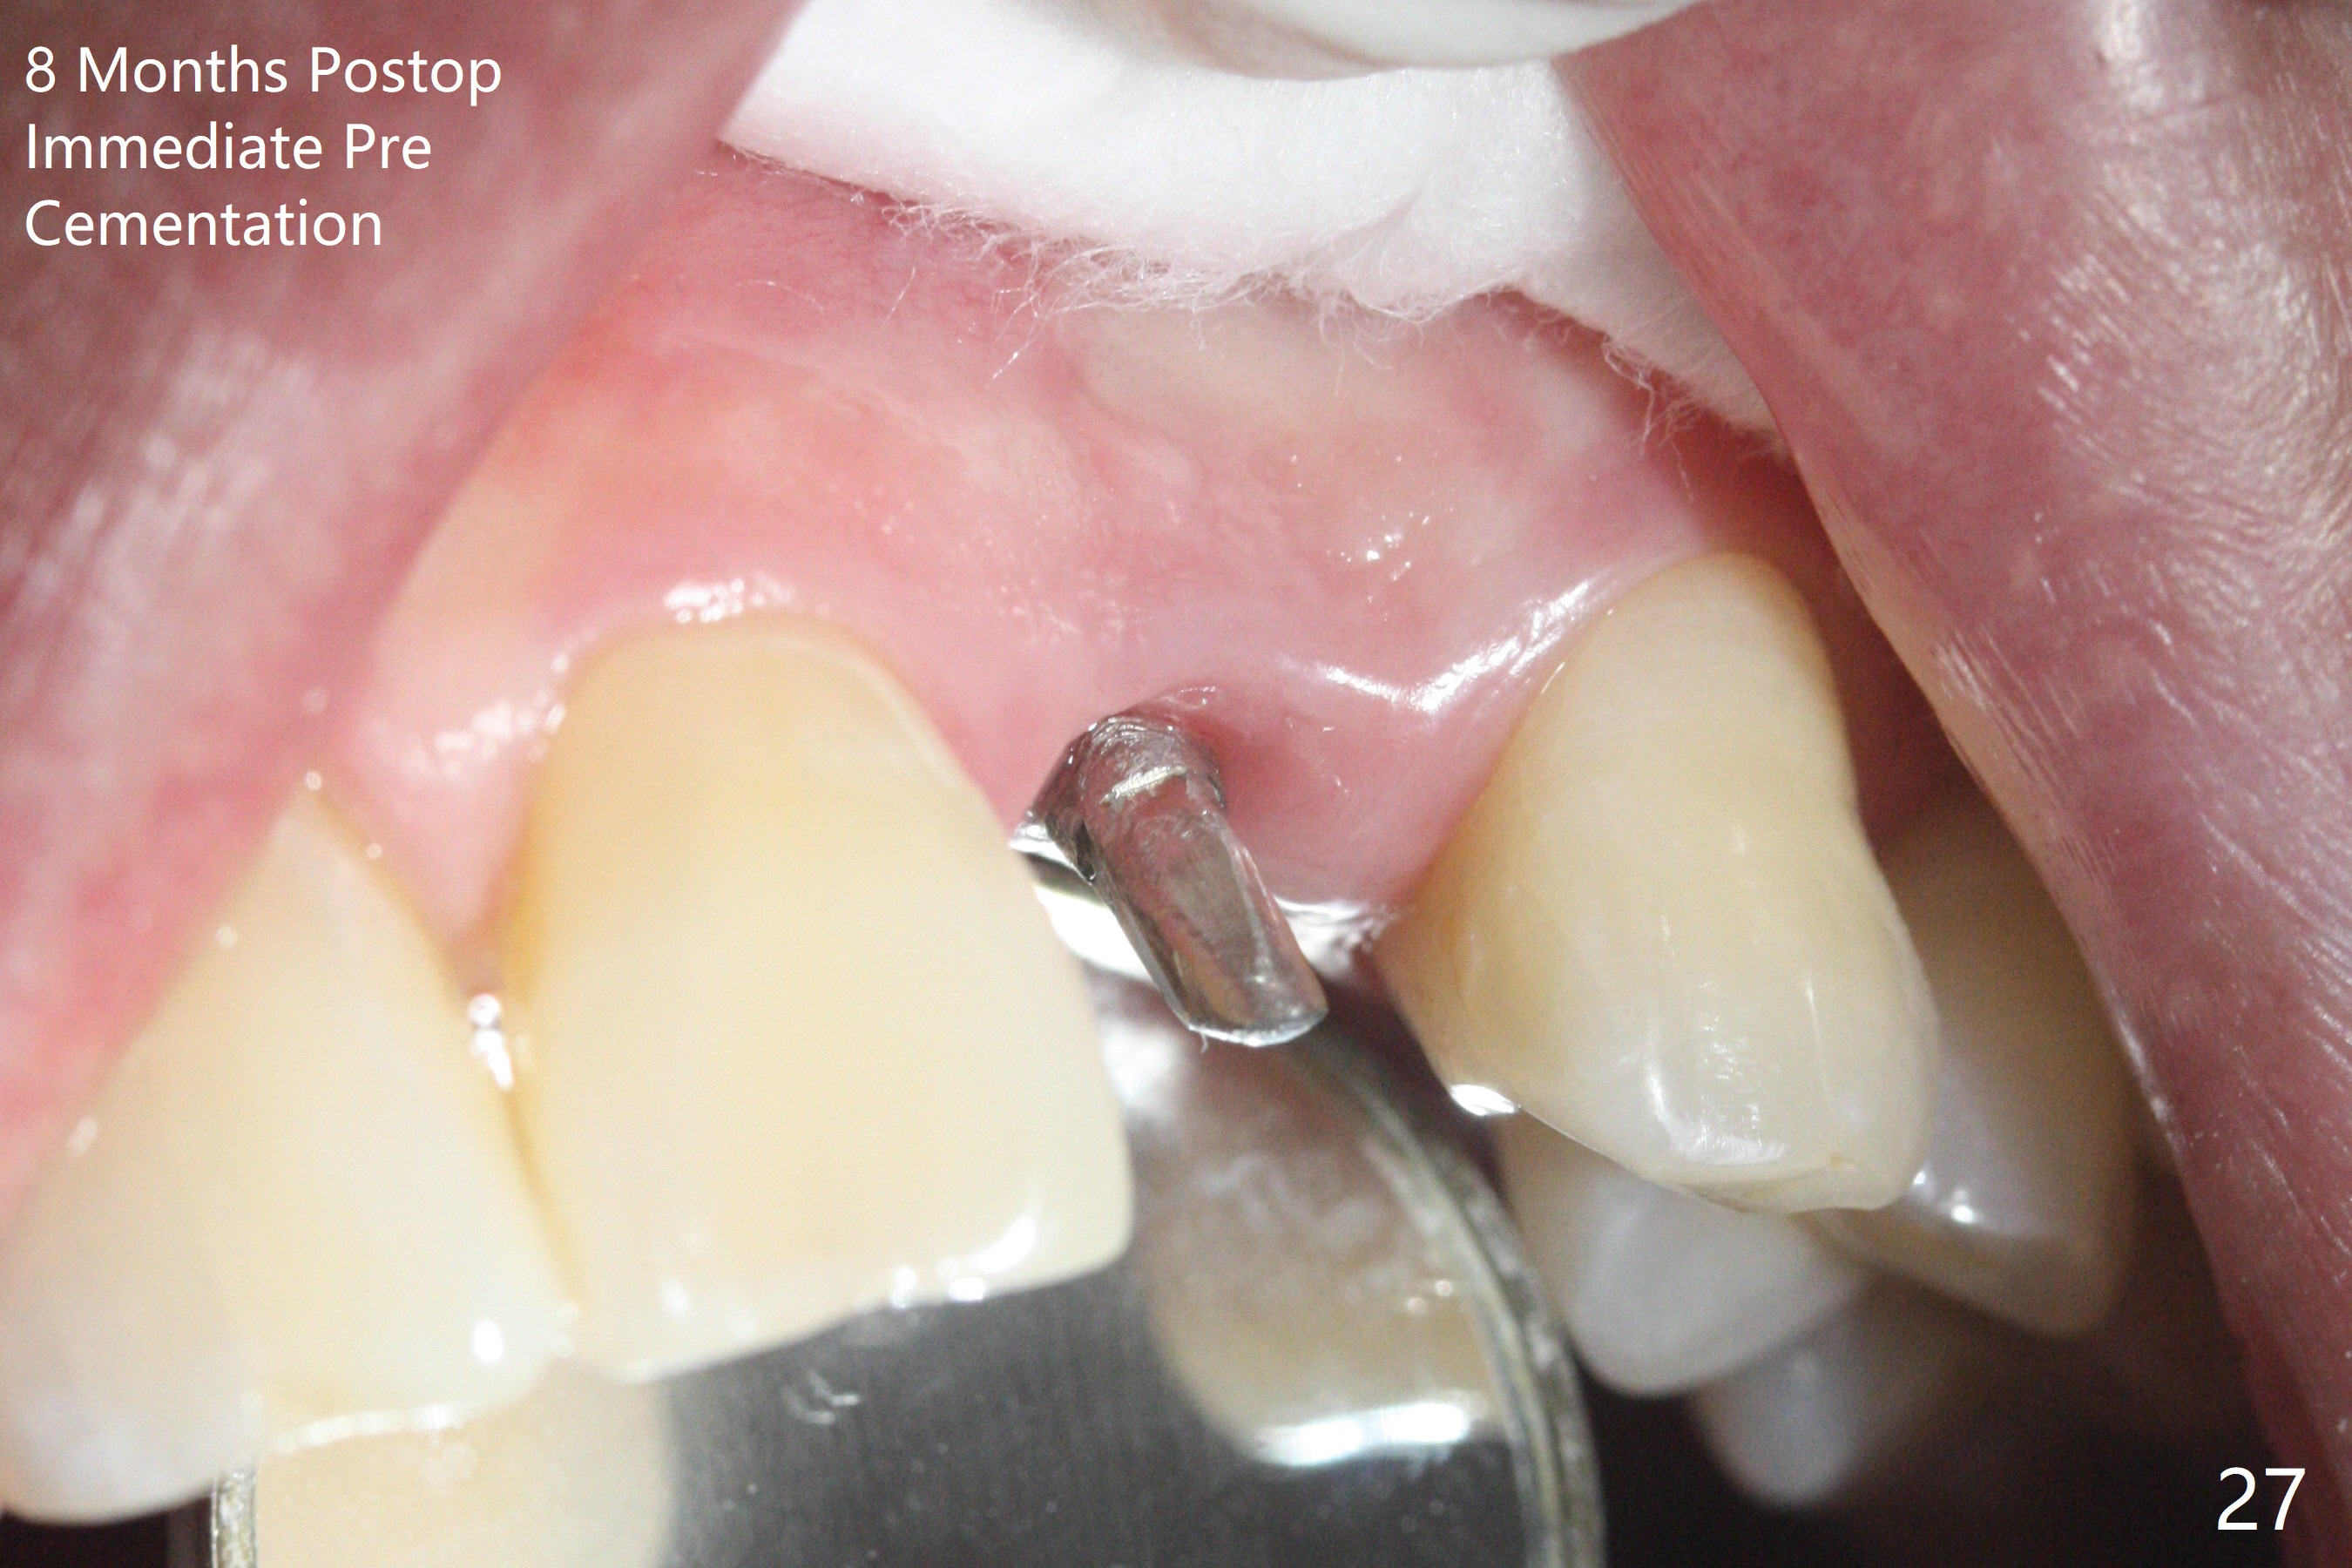

病人回来带来瘘道(图一),不过不会增加难度,病牙去除,它便自动消失。尽管颊侧骨壁完全失去,颊侧牙龈仍丰满(图二),为什么呢?第一,因为粗大牙根存在,第二两旁牙齿,牙槽骨撑着帐篷(侧切牙颊侧牙龈),第三,牙冠。为了防止术后牙龈塌陷,尽量不切开,即刻放置植体(牙根);由于前牙缘故,这次植体不能很大,所以植骨必须过度(over grafting),最后即刻制作临时牙冠,撑住牙龈。这就是所谓每个人进入角色。这个牙根有一种先天性畸形:dens in dent (图三(腭侧观):箭头)。尽管腭侧牙根畸形,腭侧骨壁吸收临床上并不严重,所以钻洞仍偏腭侧。当预定最后钻头还在钻洞时,填入大量粘性骨块(图四:*),细长植体还没有完全卡入鼻底(图五),最后好像可以(图六,七)。植体,骨粉入位(图八),最后临时牙冠出场(图九)。尽管植体小,术后一周临时牙冠仍然可以维持牙龈原有形状(emergency profile,图十:箭头(*:树脂强化牙冠固定))。图十一以不同角度显示瘘道缩小。术后三周取出有些松动的临时牙冠,骨粉虽然还没有被肉芽组织整合,但是显得正常,周围牙龈健康(图十二)。术后4个月牙龈形态正常(图十三),没有触痛;颊侧骨板轻度凹陷(图十四);骨粉仍在原位(图十五)。术后7个月骨粉仍在原位(图十五,十六,但是冠部密度减低(可能骨粉流失,需要牙周或者树脂敷料保护)),没有螺纹暴露。但是牙冠边缘暴露,说明牙龈收缩(图十七,与图十三对比),颊侧骨板仍塌陷(图十八)。插入龈线取得多个目的:修整基台边缘,取模,颊侧牙龈推向颊侧,有利于即将衬里牙冠龈缘进入龈下(图十九)。取模后牙冠边缘(图二十:<)衬里,然后修整,变窄,以便插入龈下,促进颊侧牙龈下降(图二十一,二十二)。术后8个月牙冠粘固前牙龈健康(图二十七,八),牙冠(图二十九)固位后,病人满意(图三十),咬合调整(图三十一),注意腭侧粘固粉流出通道(<)。